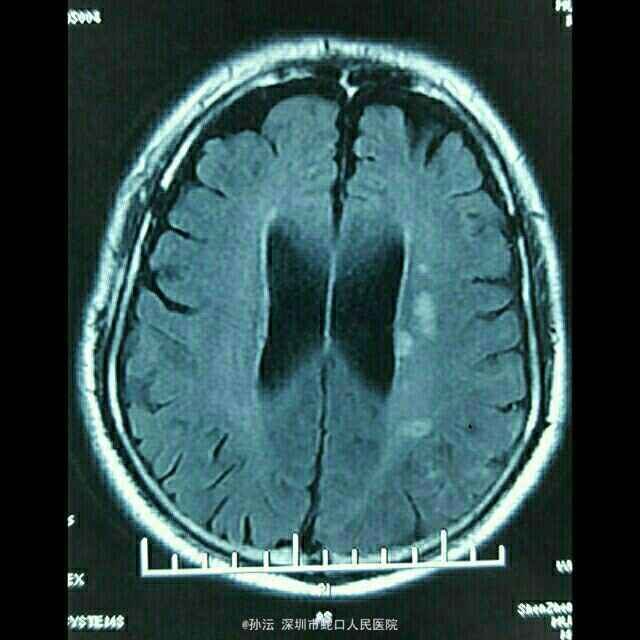

65岁男性,突发言语不利伴四肢乏力2天。 2天前无明显诱因突然言语不利,吐字不清,伴四肢乏力,以双下肢明显,表现为行走笨拙,伴肢体麻木,无头晕、头痛,无饮水呛咳、流涎,无意识不清、大小便失禁,无四肢抽搐。既往血压偏高5年,未使用降压药,血压未监测。

查体:BP 149/85mmHg,心肺听诊无异常。腹平软,无压痛、反跳痛,双下肢无水肿。神经系统检查:神志清楚,构音不清,记忆力、定向力、理解力、计算力均下降,两眼球活动自如,未见震颤,双瞳等大等圆,光反射灵敏,两侧额纹对称,右侧鼻唇沟浅,伸舌偏右,咽反射灵敏,颈软,四肢肌力5级,肌张力正常,腱反射对称,右侧病理征可疑阳性,共济征阴性,克氏征、布氏症阴性。NIHSS评分4分。 门诊头颅CT提示:脑萎缩。血液流变检测:全血粘度低切9.76mPa.s。糖化血红蛋白测定 HbA1c 6.60%。头颅MRI平扫(3.0T)示:左侧大脑分水岭区急性脑梗塞。脑小血管病变,FazekasⅡ级;轻度老年脑改变、部分空泡蝶鞍。

定位于左侧大脑中动脉及后动脉,定性动脉粥样硬化性血栓形成。 治疗上予依达拉奉清除自由基、奥拉西坦脑保护、血栓通改善微循环、阿司匹林抗血小板聚集、阿托伐他汀抗动脉硬化及对症治疗。